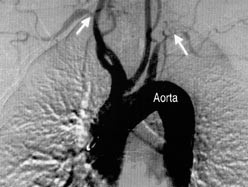

Etter utbredelsen av funnene ved angiografi inndeles tilstanden i fire typer. Ved type 1 er det kun forandringer i aortabuen og tilgrensende arterier, ved type 2 er det forandringer kun i abdominalaorta og tilgrensende arterier, ved type 3 er det forandringer i aorta og tilgrensende arterier både over og under diafragma og ved type 4 er det forandringer i pulmonalarteriene. Type 2 forekommer nesten aldri isolert. Det er ingen rase- eller aldersforskjell når det gjelder lokalisasjon eller utbredelse av sykdommen (2). Hos de fleste pasientene var stenosene ofte langstrakte, noe som skiller dem fra arteriosklerotiske stenoser (2) (fig 1). Nye, men ofte asymptomatiske stenoser er ikke uvanlig i sykdomsfoløpet.